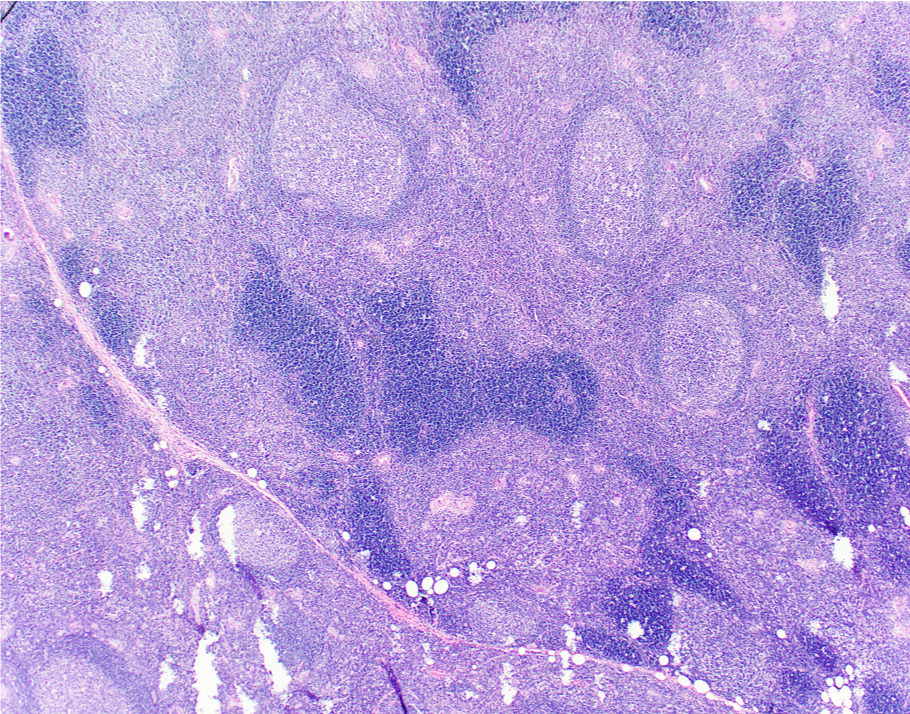

Microscopic (histologic) description

- Preserved thymic architecture

- Increased number of lymphoid follicles with prominent germinal centers of different sizes and tingible body macrophages (StatPearls: Thymic Hyperplasia [Accessed 28 February 2023], Histopathology 2009;54:69)

- Frequent Hassall corpuscles

- Rare germinal centers may be seen in the normal thymus, no clear cutoff is defined

Microscopic (histologic) images